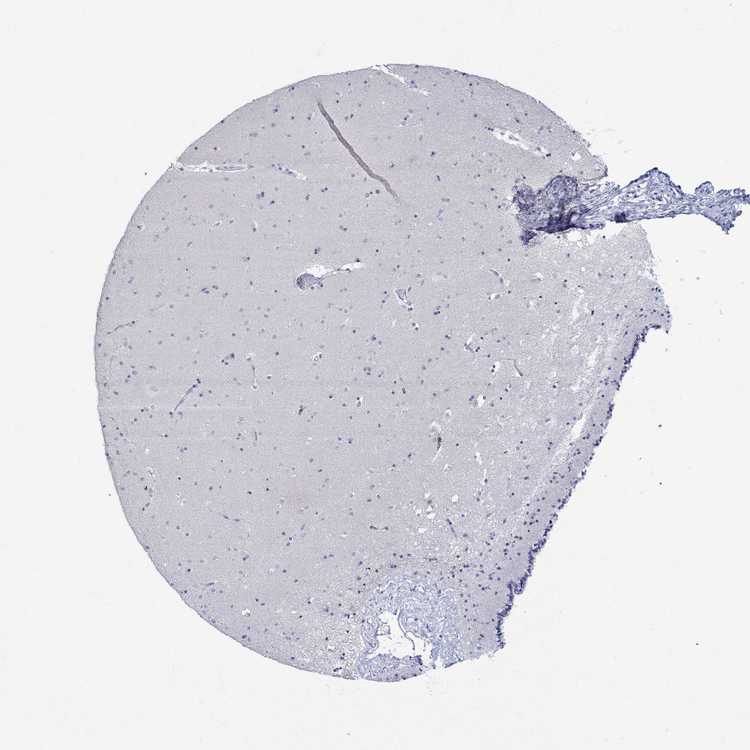

CAUDATE - Antibody stainingi

Antibody staining in the annotated cell types in the current human tissue is reported as not detected, low, medium, or high, based on conventional immunohistochemistry profiling in selected tissues. This score is based on the combination of the staining intensity and fraction of stained cells.

Each image is clickable and will lead to virtual microscopy that enables deeper exploration of all samples and also displays staining intensity scores, fraction scores and subcellular localization as well as patient and tissue information for each sample.

Antibody HPA059558

Glial cells Not detected

Neuronal cells Not detected